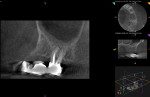

Endodontic treatment was determined to have a favorable prognosis, and such treat-ment was initiated using 2% lidocaine 1:100,000 epinephrine for anesthesia. Rubber dam isolation was achieved, and the tooth was accessed through the occlusal of the crown. The mesiobuccal (MB), mesiobuccal second (MB2), distobuccal (DB), and palatal (P) canals were located and pulpectomy was completed. The canals were filled with gutta-percha and root canal sealer (AH Plus®, Dentsply Sirona, dentsplysirona.com) using a warm vertical compaction technique (Figure 3).